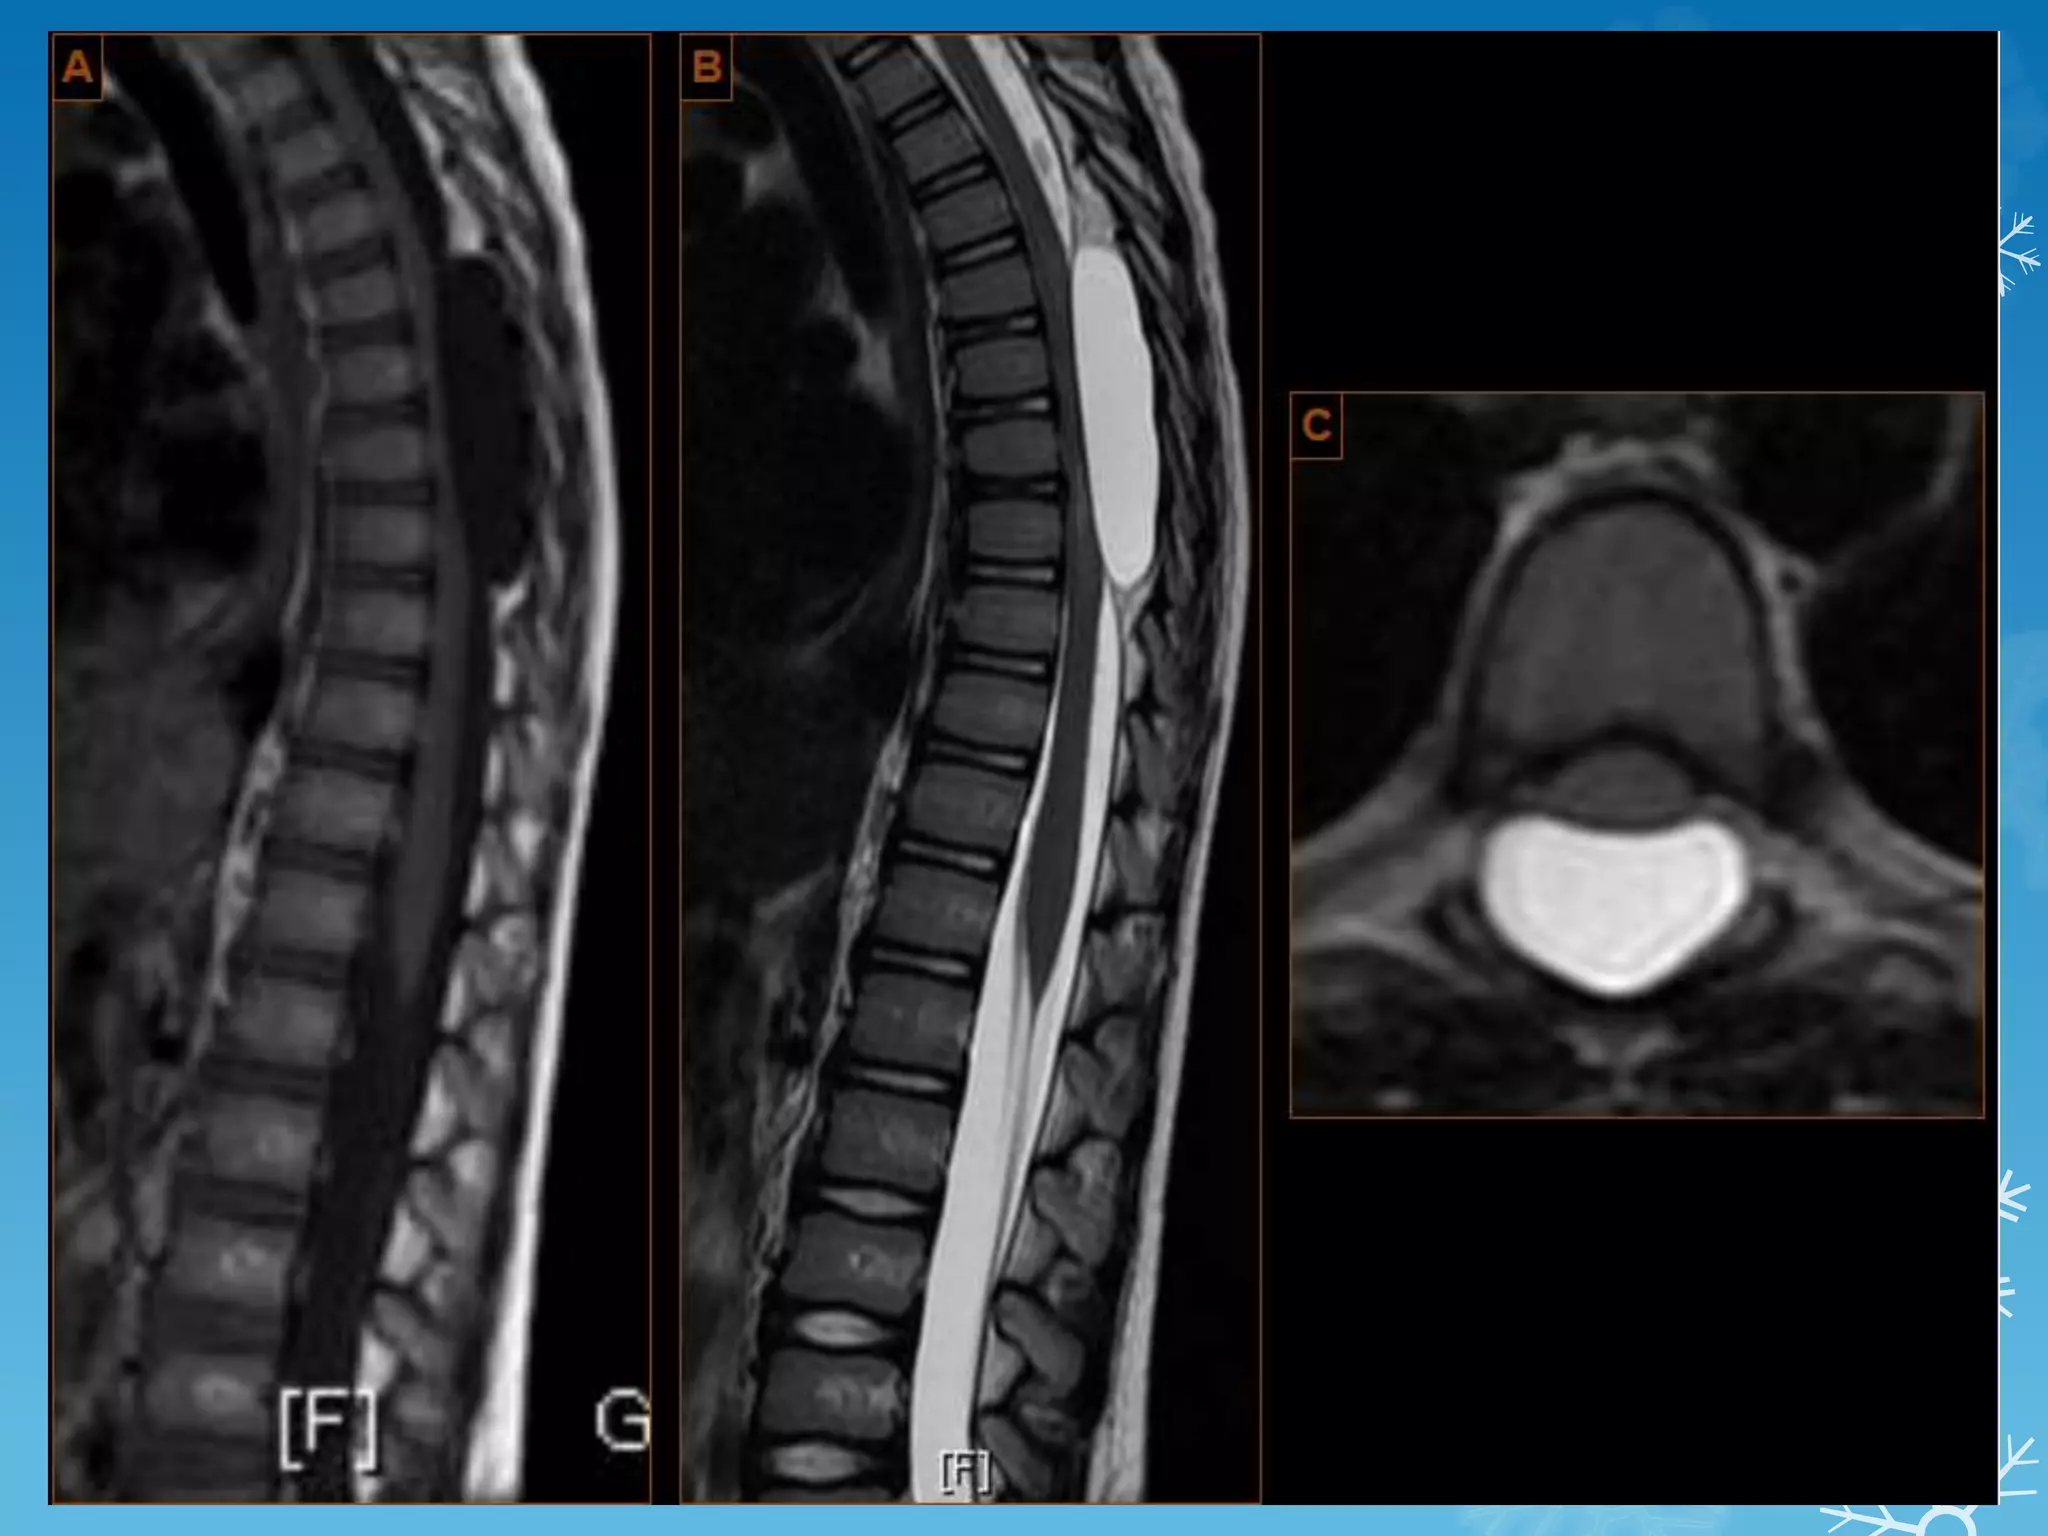

SPOT 8

4th ventricle ependymoma